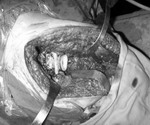

Ազդրային կոմպոնենտը մ/3-ից դեպի դիստալ բաժանվում է 4 մասի և ազդրային խողովակի մեջտեղադրելու ժամանակ օգտագործելով մետաղական հիշողությունը, լայնանում է մարմնի ջերմաստիճանիազդեցության տակ ապահովելով իրեն ստաբիլությունը (նկ. 2):

Նկ. 2. Բնական քացախափոսը զննելուց առկա էր վերին-հետին պատի դեֆեկտ մոտ 35-40%-ի չափով: Կատարվեց այդ հատվածի աուտոպլաստիկա, տրանսպլանտատը վերցնելով աջ նրբոլոքի դիաֆիզիցսմ երկարության չափի խողովակավոր ոսկր, որը բաժանվեց 4սմ և 6 սմ չափի: Տալովտրանսպլանտատներին տեղադրմանը հարմար ձև` դրանք ֆիքսվեցին 2-ական կորտիկալ պտուտակներով: 10